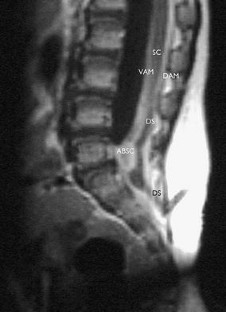

Cases of infected dermal sinus are scarce and detailed surgical anatomical descriptions are hardly found in literature. The clinical, radiological, and surgical findings in four cases of an infected dermal sinus located at the lower spine are presented to elucidate the pathological anatomical configuration.

The first case showed two dermal sinuses with a parallel course extra- and intradurally, ending in a confluence of cavities connected to the conus. In this case, as well as in the fourth case, the signs and symptoms were those of meningitis. The second case presented with meningitis and a subdural empyema, while the third case presented with an intradermoid–intramedullary abscess at the junction between the DS and the conus. This child probably showed signs and symptoms of conus involvement as early as during pregnancy.

The anatomy of the nervous elements in this congenital anomaly is heavily disturbed, more particularly in case of infection, due to extensive arachnoidal scarring. The latter renders dissection laborious and recognition of anatomical details difficult, resulting in complete excision of a dermal sinus in less than half of the cases. Despite their variability in presentation, most cases of an infected dermal sinus show similar characteristic features.